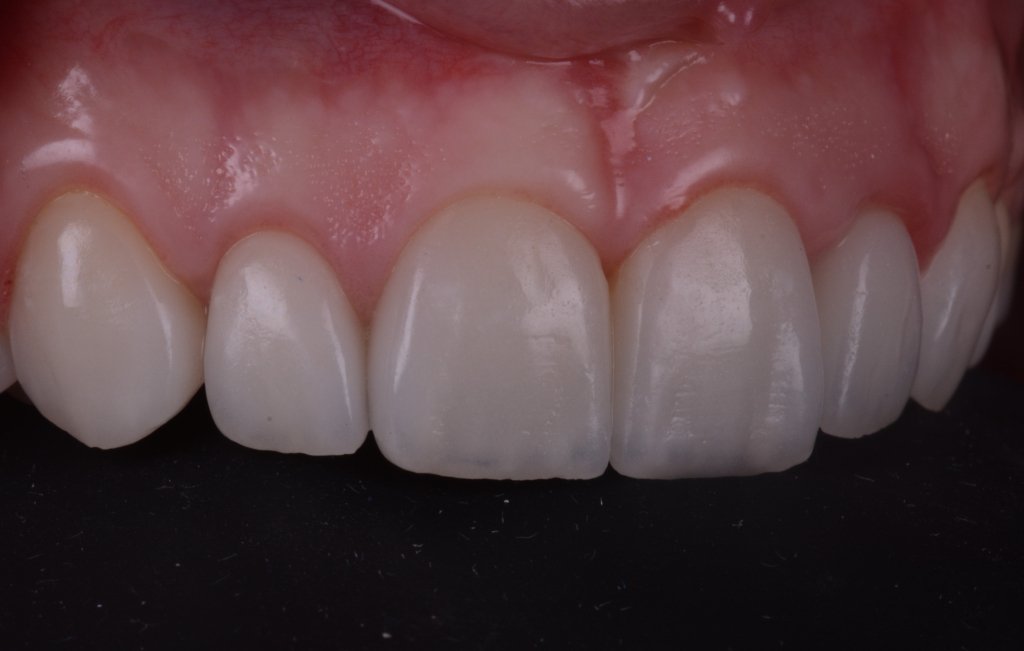

No me asusta esta ligera inflamación, al revés se que están pasando cosas buenas, la encía se esta estabilizando y engordando según los principios de la técnica BOPT. Así que tengo tiempo para disfrutar simplemente del trabajazo de Nacho.